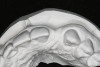

Figure 13   Exploiting study casts for planning single-tooth implant placement and restoration: Mounted study casts permit an estimation of available bone volume (Fig 13); measure the bound edentulous space inter-tooth dimensions (Fig 14); measure the available inter-arch dimension (restorative space) (Fig 15); and evaluate alveolar ridge/tooth relationships (distance from zenith represented by plastic stent to ridge crest) (Fig 16).

Figure 13

Figure 14   Exploiting study casts for planning single-tooth implant placement and restoration: Mounted study casts permit an estimation of available bone volume (Fig 13); measure the bound edentulous space inter-tooth dimensions (Fig 14); measure the available inter-arch dimension (restorative space) (Fig 15); and evaluate alveolar ridge/tooth relationships (distance from zenith represented by plastic stent to ridge crest) (Fig 16).

Figure 14